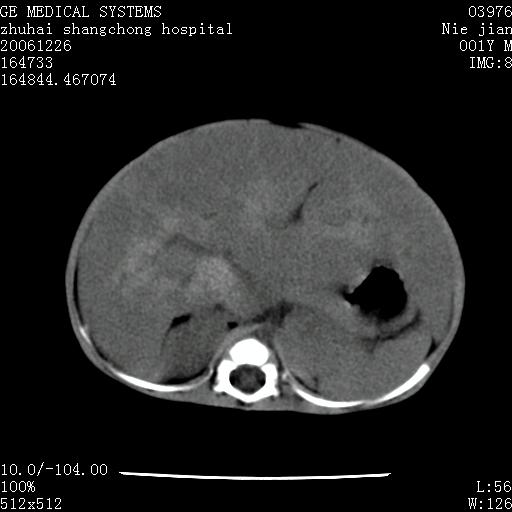

3个月婴儿腹胀来看。

【影像特征】

1、肝明显增大,肝弥漫性低密度灶。

2、肾上腺区见类圆形肿块,其内密度不均,见片状偏高密度。

【诊断】

1、肝弥漫性病变,考虑急性肝炎致广泛脂肪浸润可能性大。

2、肾上腺区占位,假性肿瘤?肾上腺血肿(感染所致)?

1、关键着眼点:肝脏弥漫性病变内有没有走形的血管,仔细看部分低密度内有血管影(要有增强扫描作为证据就好了),说明并非肿瘤样病变,而是脂肪浸润。即可能不是转移瘤或原发肿瘤,低密度的形态上看,是片状,也不像肿瘤。

2、儿童肝炎最常见的是感染,有时食入性损害或药物也可致肝脏炎症,肝炎致大空泡型脂肪变性,是一种无痛性疾病,无症状,病因有营养异常、代谢性疾病、药物及病毒感染。所以脂肪变性与感染有关。

3、肝炎的结局是肝硬化,而恰恰一年后复查,已有肝硬化表现。肿瘤一般那会消失,那叫奇迹。

4、肾上腺出血也可见于败血症及感染,通常包块在数周内消失,ct表现包块内有偏高密度,可能是亚急性血肿的表现。假性肿瘤即腹部肠管积液、扩张血管及邻近结构的伪像。自然会消失。

5、因此,感染可以贯穿一切,解释一切。肿瘤自然消退?可能吗?那些应要无道理的创造奇迹的事情会那么容易发生吗?